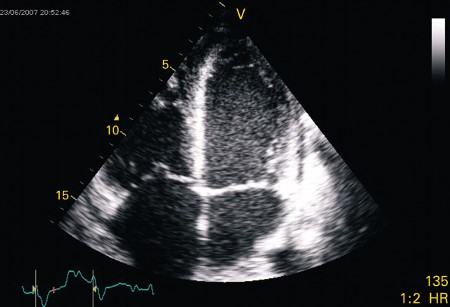

Apical 4-chamber echocardiogram in a patient presenting with myocarditis showing a slightly dilated left ventricle with spontaneous ultrasonic contrast indicating severely impaired left ventricular systolic function

From: Rasmussen TB, Dalager S, Andersen NH, et al. BMJ Case Reports 2009; doi:10.1136/bcr.09.2008.0997